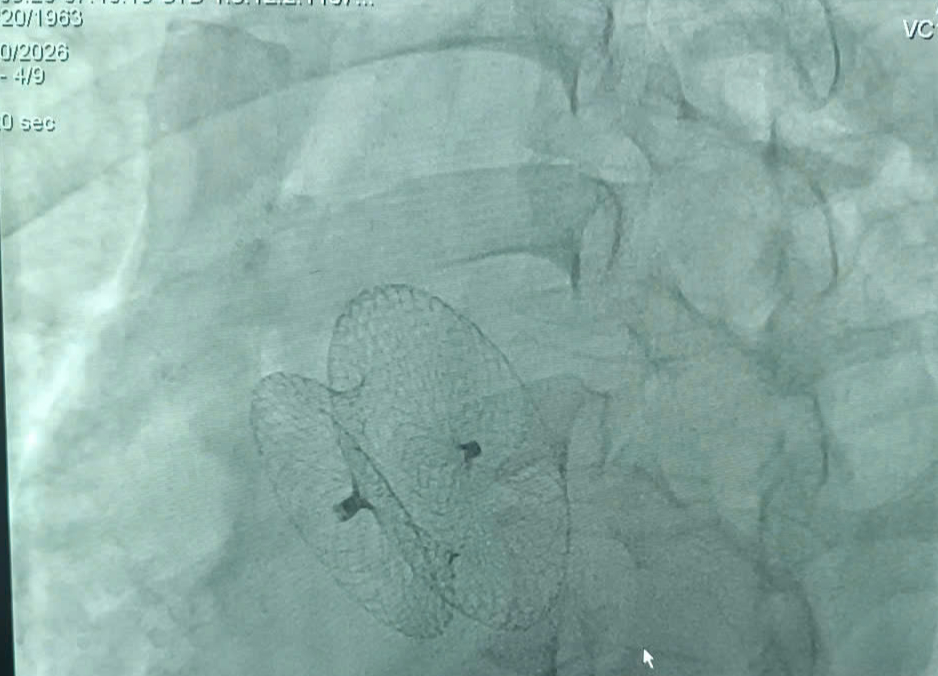

Bệnh nhân mắc thông liên nhĩ - một dị tật tim bẩm sinh. Ảnh: Bác sĩ cung cấp.

Bệnh nhân được can thiệp bít lỗ thông liên nhĩ

Qua thăm khám và xét nghiệm, bác sĩ xác định người bệnh mắc thông liên nhĩ – dị tật tim bẩm sinh với lỗ thông lớn khiến buồng tim phải giãn. Đồng thời, bệnh nhân đã xuất hiện rung nhĩ, một dạng rối loạn nhịp nguy hiểm.

Trước đây, phương pháp điều trị chủ yếu là phẫu thuật mở ngực, xâm lấn lớn và cần thời gian hồi phục dài. Hiện nay, với sự phát triển của tim mạch can thiệp, kỹ thuật bít lỗ thông qua da giúp đóng dị tật mà không cần mổ, giảm đau và rút ngắn thời gian nằm viện.